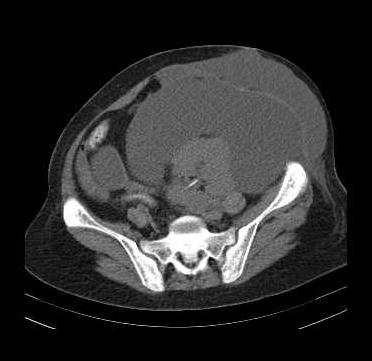

Sarcoma mỡ sau phúc mạc (Retroperitoneal liposarcoma)

16/03/2026